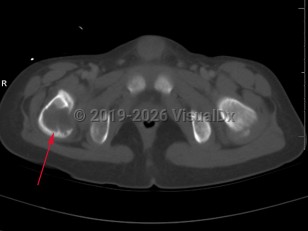

Langerhans cell histiocytosis (LCH) refers to a spectrum of diseases that includes eosinophilic granuloma (EG), Hand-Schuller-Christian disease, and Letterer-Siwe disease. EG is a rare (seen in 1-5 per million), benign tumor-like disorder that features clonal proliferation of Langerhans cells (antigen-presenting mononuclear cells of dendritic origin) usually found in bones; however, this can involve other organ systems. EG occurs most often in children aged 5-15 years, with a male-to-female ratio of 2:1. EG constitutes 60%-80% of cases of LCH and accounts for less than 1% of all bone tumors. Ninety percent of cases involve a single lesion, usually in the axial skeleton, with just under 10% of cases involving lesions in multiple bones or lesions in other organ systems (ie, skin, pituitary gland, gastrointestinal [GI] tract, lung, spleen, or brain).

The clinical presentation of EG depends largely on the location affected. EG is most often confined to the axial skeleton. EGs are often asymptomatic and found incidentally, or may initially present with pain and swelling of the affected area, with or without decreased range of motion. Commonly affected areas of the skeleton include (in order of frequency): skull, femur, pelvis, mandible, clavicle, ribs, and long bones (of the diaphysis and metaphysis).